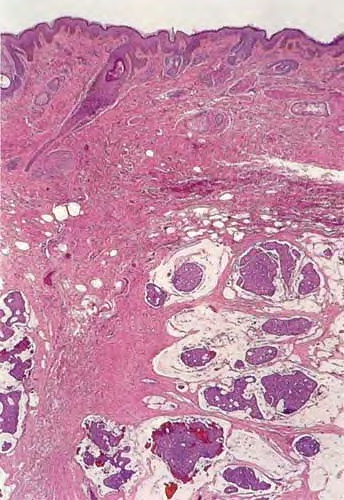

There are solid and cystic aggregations of neoplastic cells within the dermis, often with extension to the subcutis, embedded in large pools of mucin. Mucinous areas are typically separated by fibrous septae.